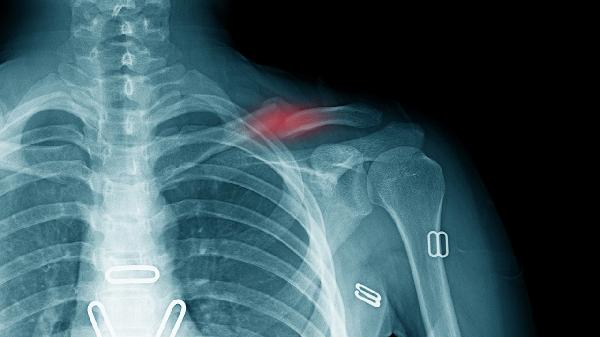

术后48小时需复查鼻内镜,通过影像学确认骨折端对位情况。医生将综合肿胀程度、通气功能及疼痛评分决定最终取出时间,部分患者可能需分次取出填塞物。